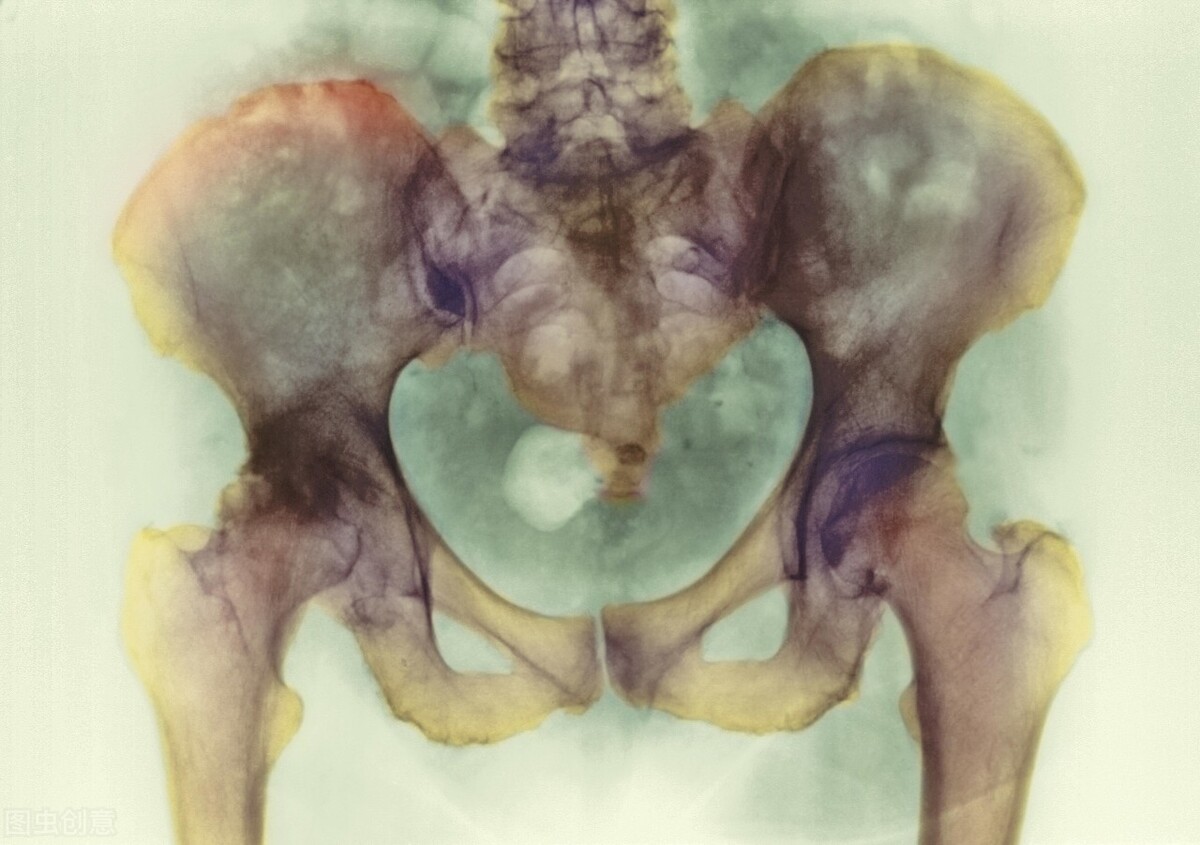

女性生殖系统的疾病即为妇科疾病,包括外阴疾病、阴道疾病、子宫疾病、输卵管疾病、卵巢疾病等。

女性盆腔炎

盆腔炎又分为急性盆腔炎和慢性盆腔炎。急性盆腔炎的症状主要是下腹痛、发热,阴道分泌物增多,腹痛持续性发作,一般会在活动或者*生活性**后更为加重;慢性盆腔炎则是会出现下腹部坠胀,疼痛以及腰骶部酸痛等症状,多发生在疲劳、*生活性**以及月经前后。

附件炎(输卵管炎症、输卵管堵塞、卵巢炎、多囊卵巢,囊肿,卵巢早衰和功能下降);